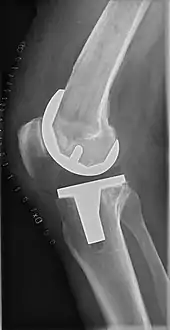

Technique

The surgery involves exposure of the front of the knee, with detachment of part of the quadriceps muscle (vastus medialis) from the patella. The patella is displaced to one side of the joint, allowing exposure of the distal end of the femur and the proximal end of the tibia. The ends of these bones then are cut accurately to shape, using cutting guides oriented to the long axis of the bones. The cartilages and the anterior cruciate ligament are removed; the posterior cruciate ligament also may be removed but the tibial and fibular collateral ligaments are preserved.[18] Whether the posterior cruciate ligament is removed or preserved depends on the type of implant used, although there appears to be no clear difference in knee function or range of motion favoring either approach.[18] Metal components are then impacted onto the bone or fixed using polymethylmethacrylate (PMMA) cement. Alternative techniques exist that affix the implant without cement. These cement-less techniques may involve osseointegration, including porous metal prostheses. Finally, stability and range of motion are checked, followed by irrigation, hemostasis, placement of hemovacs, and closure.[19]

Femoral replacement

A round-ended implant is used for the femur, mimicking the natural shape of the joint. On the tibia the component is flat, although it sometimes has a stem that goes down inside the bone for further stability. A flattened or slightly dished high-density polyethylene surface is then inserted onto the tibial component so the weight is transferred metal to plastic, not metal to metal. During the operation any deformities must be corrected, and the ligaments balanced so the knee has a good range of movement, and is stable and aligned. In some cases the articular surface of the patella also is removed and replaced by a polyethylene button cemented to the posterior surface of the patella. In other cases, the patella is replaced unaltered.